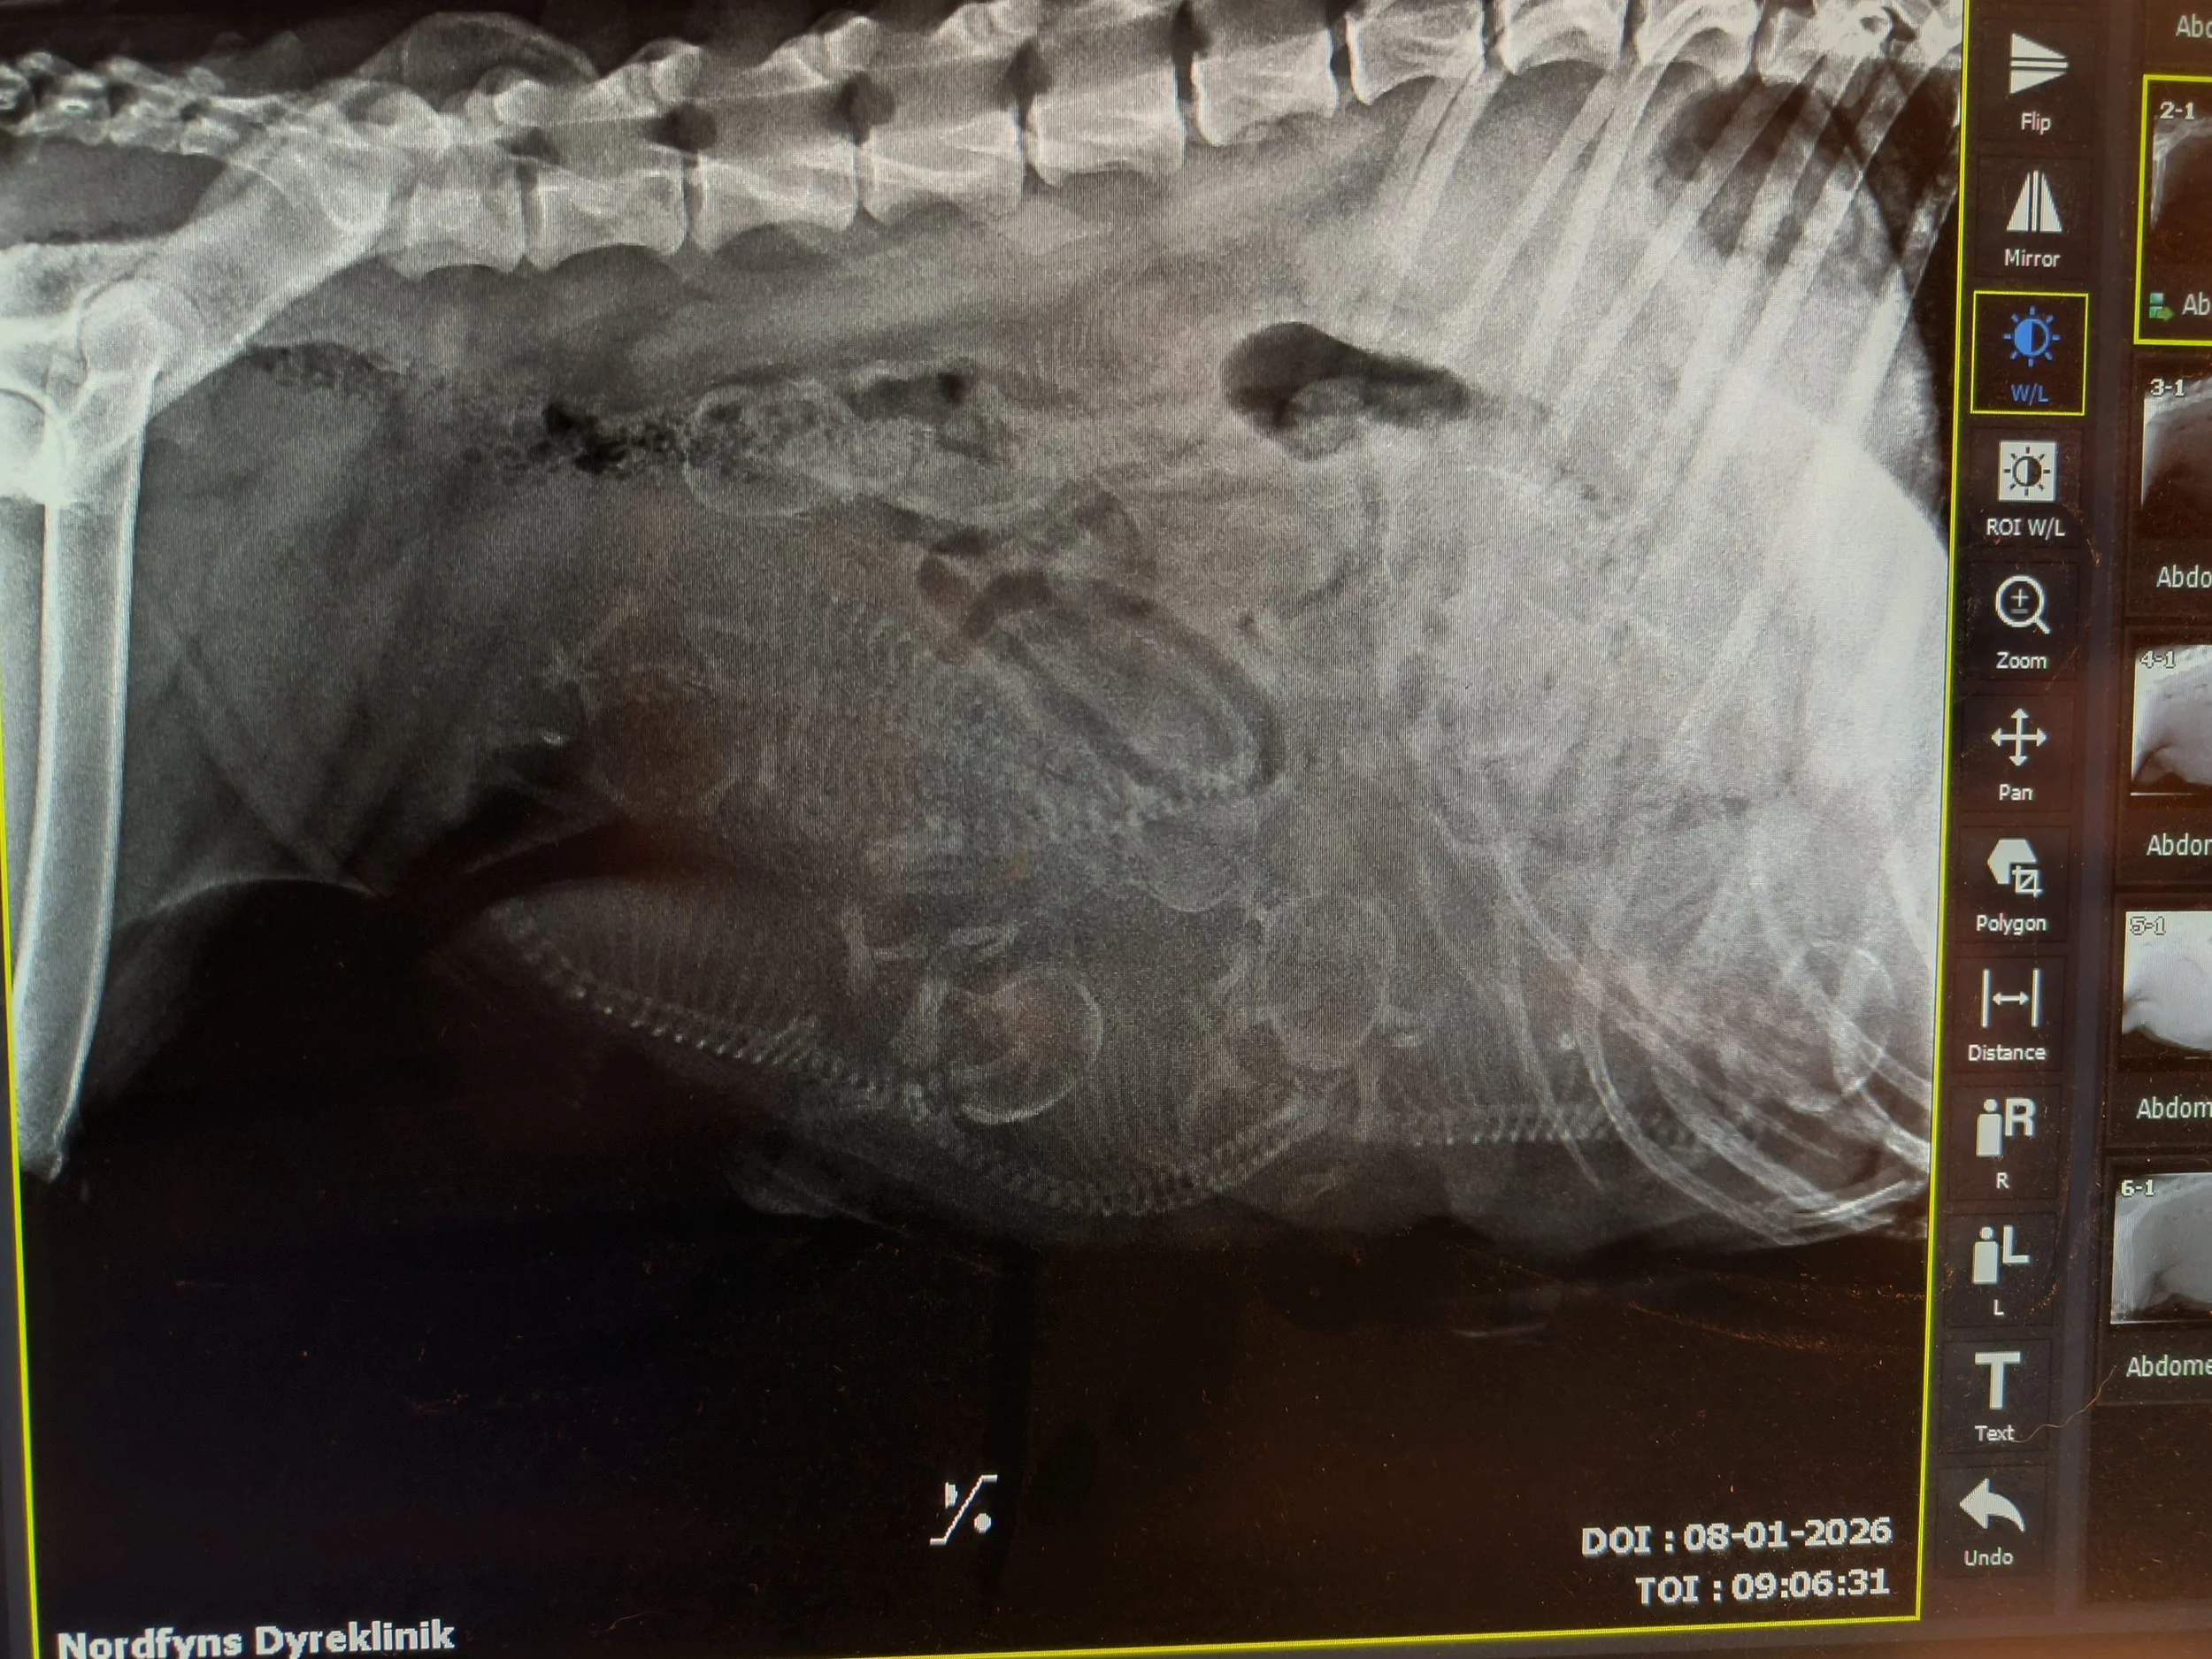

Am 8. Januar wurde Juno geröntgt. 7 Welpen waren da, und jetzt war es nur abwarten, und endlich, am 15. Januar, war es so weit. Leider gab es Komplikationen, so ab zum TA, und Juno hatte einen Kaiserschnitt. 2 Welpen waren leider 1 - 2 Tage vor der Geburt im Gebärmutter gestorben, aber Juno brachte 5 schöne Welpen mit nach Hause - 4 Mädchen und einen ganz kleinen Jungen. Obwohl wir von Anfang an zugefüttert haben, hat er es leider nicht geschafft - er hat getrunken, aber nicht zugenommen, und nach 6 Tage müssten wir zusammen mit unsere TA erkennen, dass unser kleinen Cliff nicht bereit für das Leben war. Laut unserem TA waren Cliffs Verdauungs Organe nicht fertig entwickelt. Es tut weh, aber jetzt liegt der kleine im Garten begrabt, zusammen mit unseren anderen toten Familien Tiere. Und wir freuen uns sehr über Cove, Caey, Cape und Crest. Die fühlen sich wohl und werden jeden Tag grösser. Juno ist eine tüchtige Hunde Mama und kümmert sich ausgezeichnet um ihre Babies.